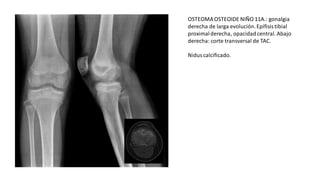

OSTEOMAOSTEOIDE NIÑO 11A.: gonalgia

derecha de larga evolución.Epífisis tibial

proximalderecha, opacidadcentral. Abajo

derecha: corte transversal de TAC.

Nidus calcificado.